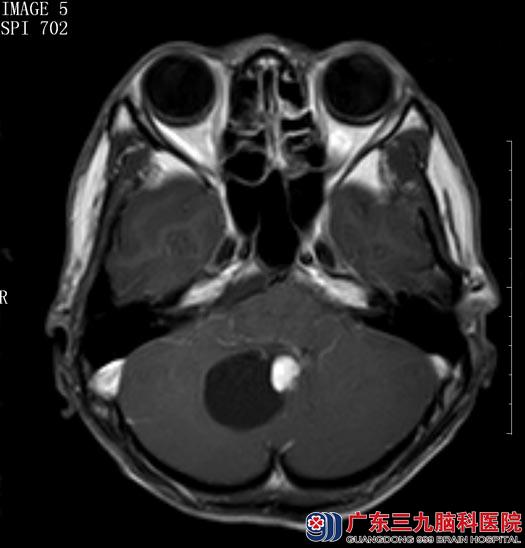

广东三九脑科医院核磁共振检查结果:“右侧小脑半球囊实性占位,实性部分直径约2cm,考虑血管母细胞瘤”。

综合神经外科鲁明主任阅片后认为:结合患者病史、症状、体征及头颅MR检查,考虑右侧小脑半球血管母细胞瘤,肿瘤呈囊实性,对小脑半球及脑干有压迫,手术指征明确。

▲手术前